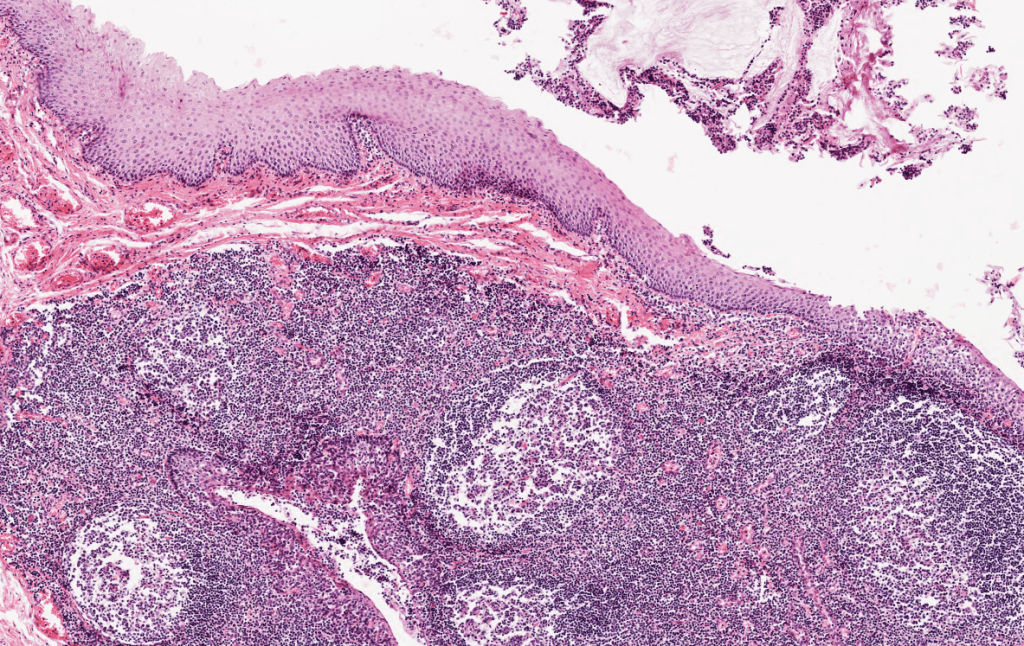

AMÍGDALAS

Faríngeas: revestidas de epitelio respiratorio. Palatinas: revestidas de epitelio plano estratificado.

Observe el epitelio respiratorio que reviste las tonsilas faríngeas.Las amígdalas son acúmulos diferenciados de folículos linfoides situados debajo del epitelio de revestimiento de los puntos de entrada al tubo digestivo y al aparato respiratorio.Identifique el epitelio de revestimiento y las criptas palatinas.Las criptas palatinas son espacios en forma de «grietas» y son características de las amígdalas.El epitelio plano estratificado sin estrato córneo reviste las tonsilas palatinas,Amígdala palatina, HyE. Observe los nódulos linfoides secundarios.Recuerda que la amigdalitis es especialmente común en los niños y a menudo acompaña a una faringitis. Amígdala palatina, HyE.Las amígdalas son estructuras parcialmente encapsuladas que carecen de vasos linfáticos aferentes pero que están drenadas por vasos linfáticos eferentes. Amígdala palatina, HyE.Observe la enorme cantidad de nódulos linfáticos que tienen las amígdalas. Amígdala palatina, HyE.